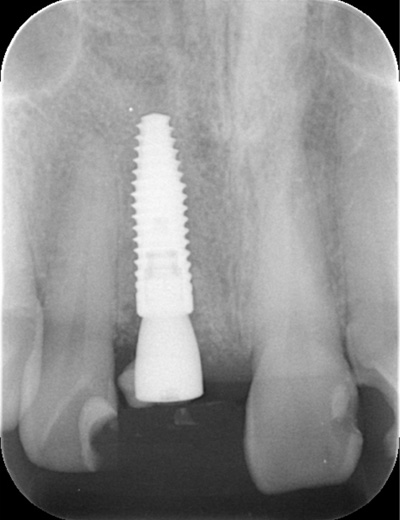

| 年代・性別 | 30代 女性 |

|---|---|

| 主訴 | 左上の乳歯がグラグラしてきた |

| 治療期間 | 約12ヶ月 |

| 費用 | 550,000円 |

| 治療内容 | インプラント、骨造成、セラミック修復 |

| 治療に伴うリスク | インプラント周囲炎 セラミックの破折、脱離 |